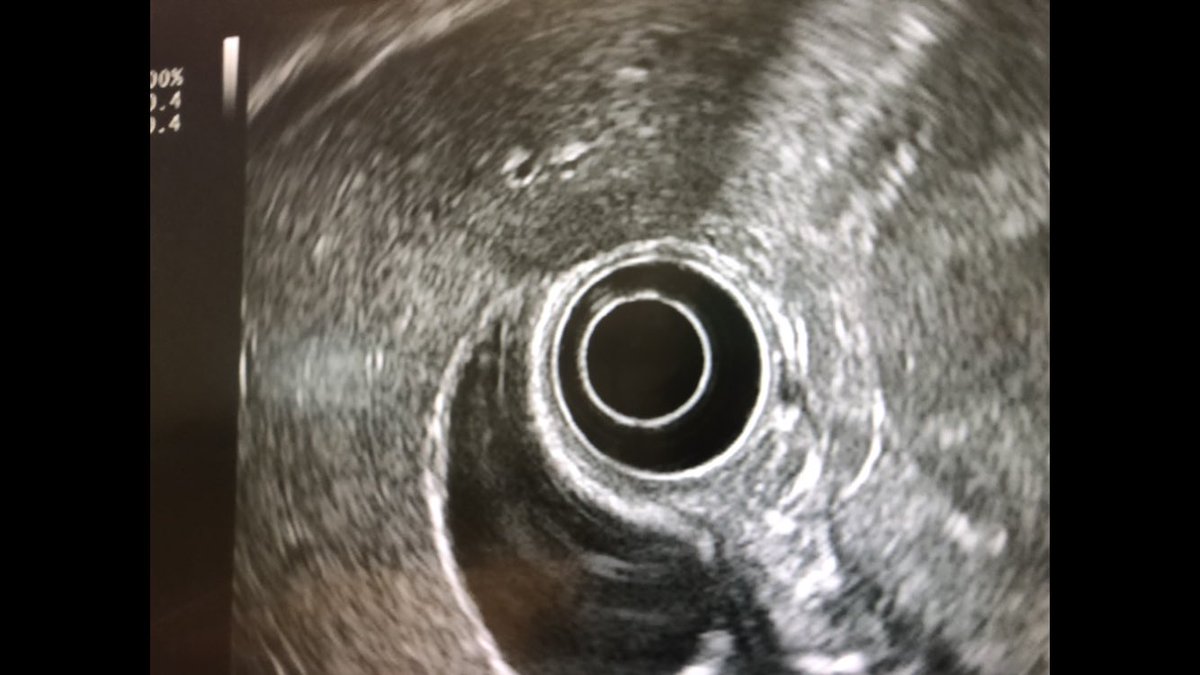

Ampullary cancer

منظار الأشعة الصوتية يظهر انسداد القناة المرارية الرئيسية بورم في فتحة اوددي. أعراض المرض صفار والتهاب في القنوات المرارية في بعض الأحيان. قد يشخص خطئا بحصوة في القناة المرارية إذا لم يتم عمل أشعة النظار الصوتية

#endoscopicultrasounds